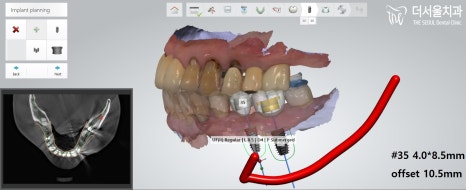

이때, 성남치과 는 구강 속을

디지털 스캔 장비를 이용하여 본뜹니다.

스캔이 완료되었을 때,

그 데이터를 기반으로

모의 수술을 진행하며

가이드 제작에 들어갑니다.

이런 식으로 각 위치마다 조심해야 될 점,

뼈의 길이나 너비는 어떻는지,

신경관과 가깝지는 않은지,

뼈이식을 추가로 해줘야 되는지 등

여러 가지를 살펴보며 체크해줍니다.

위치와 각도를 모두 최종적으로 결정내리면,

그 데이터를 기반으로 가이드를 제작합니다.